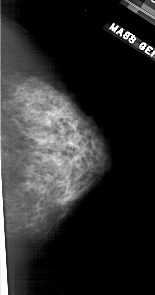

A_1709_1.LEFT_MLO

LEFT_MLO LINES 5491 PIXELS_PER_LINE 2986 BITS_PER_PIXEL 12 RESOLUTION 43.5 OVERLAY